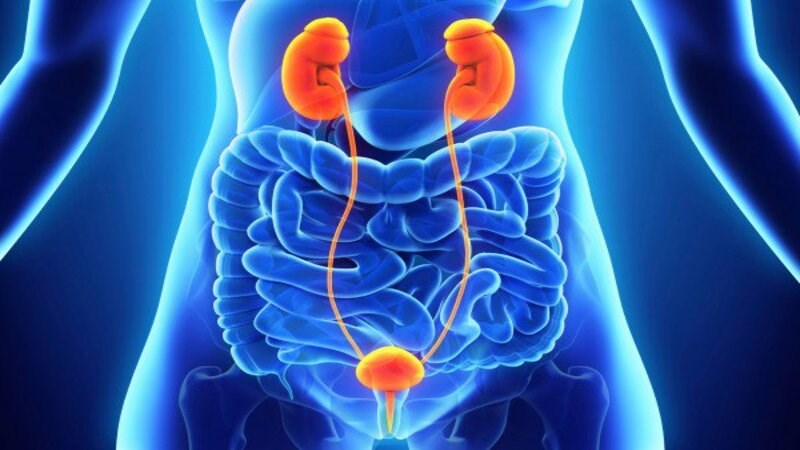

Hệ thống tiết niệu của chúng ta bao gồm thận, niệu quản, bàng quang và niệu đạo. Tất cả những bộ phận này đều đóng vai trò loại bỏ các chất thải ra khỏi cơ thể qua nước tiểu.

Trong đó, niệu quản sẽ mang nước tiểu từ thận xuống bàng quang, nơi nước tiểu được lưu trữ cho đến khi thoát ra khỏi cơ thể qua ống niệu đạo trong quá trình đi tiểu.